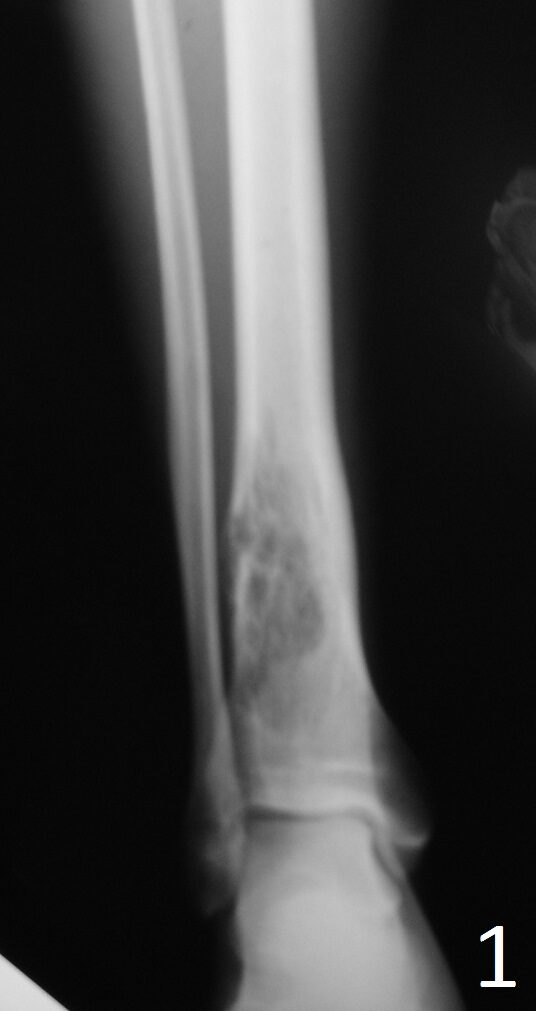

Plain x-ray (Fig. 1-2)

• Well-defined, lucent and expansile

• Possible cortical degradation

• Possible involvement of soft tissue

• More destructive, aggressive growth

• Shown by less-defined borders

• Pathologic fracture may occur

• Described as moth eaten